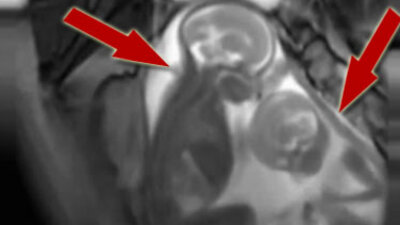

Anasayfa Video Sağlık Anne karnında kavga!